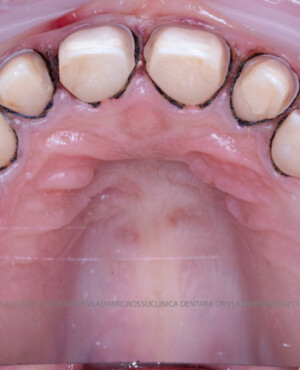

Cazuri clinice

Caz 1

Caz 2